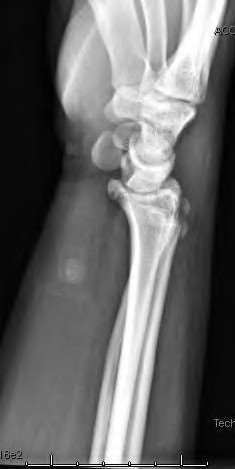

A 20-year-old park ranger trips and falls onto his right wrist with the wrist in extension and pronation. The local urgent care orders both radiographs and a CT, which you review and determine to be normal. The patient complains of ulnar-sided wrist pain. On exam, his tenderness is localized to the fovea. Ulnar deviation also causes him pain. There is no snapping sensation with wrist supination, flexion, and ulnar deviation. He otherwise has 5/5 strength to his first dorsal interosseous muscle with 4mm static two-point discrimination on the ulnar side of the 4th digit. Which of the following injuries is most likely responsible for his symptoms and exam?